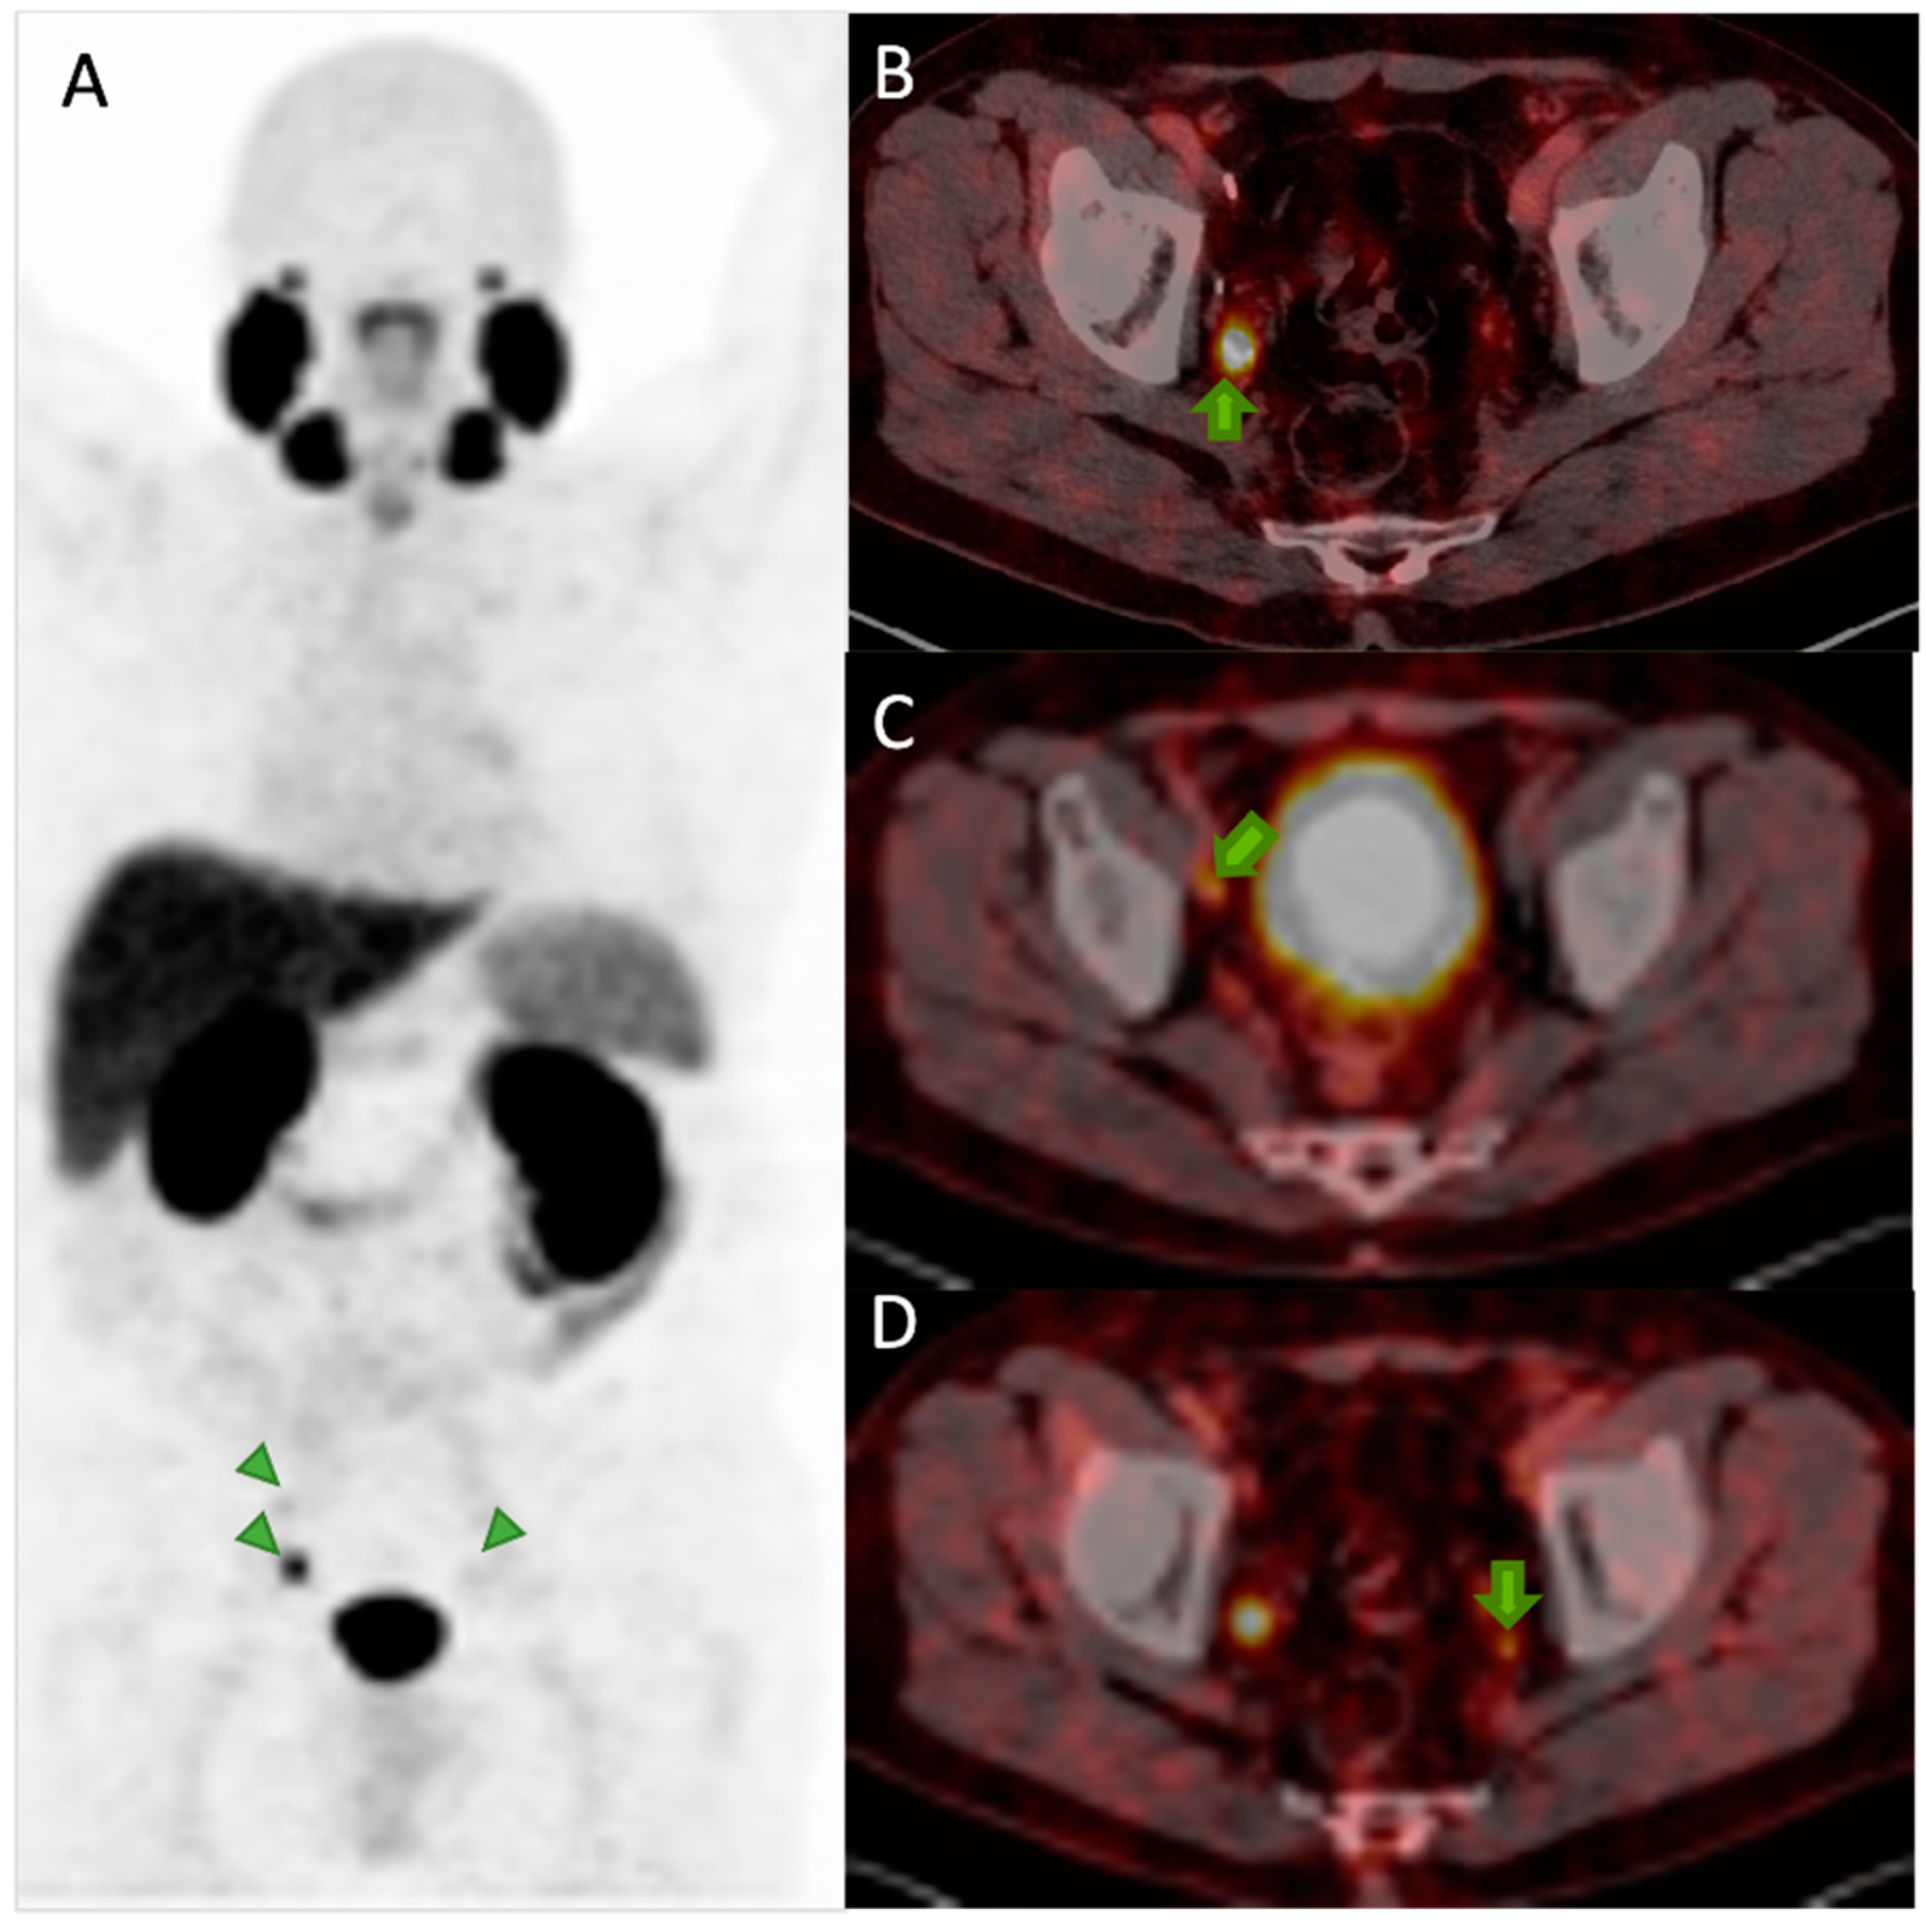

6. Diagnosis with PSMA PET/CT

6.3. Detection of Biochemical Recurrence

6.4. Assessment of Response to Treatment